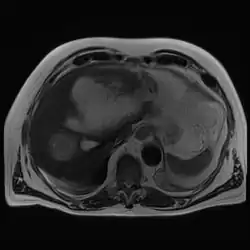

| Amoebic hepatic abscess | |

| Gross pathology of liver containing amoebic abscess | |